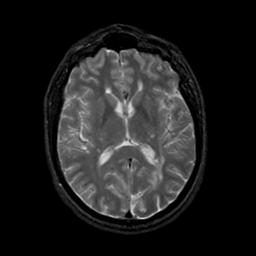

MR Study #19, August 25, 1991 -- Slice #27

[Home][Help][Clinical][Tour 1][Tour 2] Slice 27